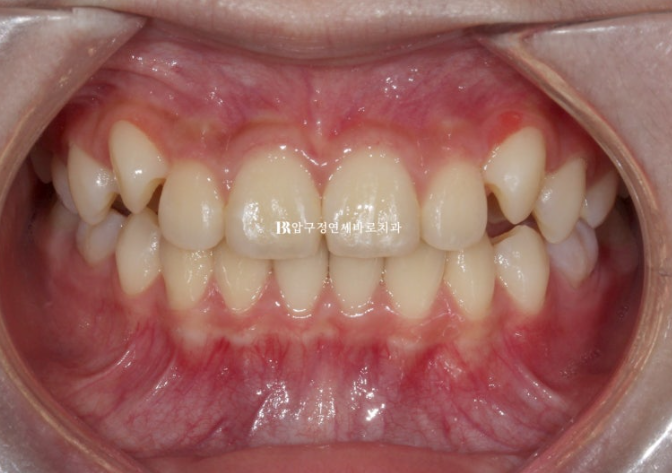

마지막 장치를 낀 후 모습입니다.

24.07

덧니처럼 나와있던 송곳니는 잘 배열이 되었고 그 사이 마지막 유치 어금니 4개가 빠지고 영구치 작은 어금니가 내려오는 중입니다.

드디어 영구치열에 접어들었습니다.